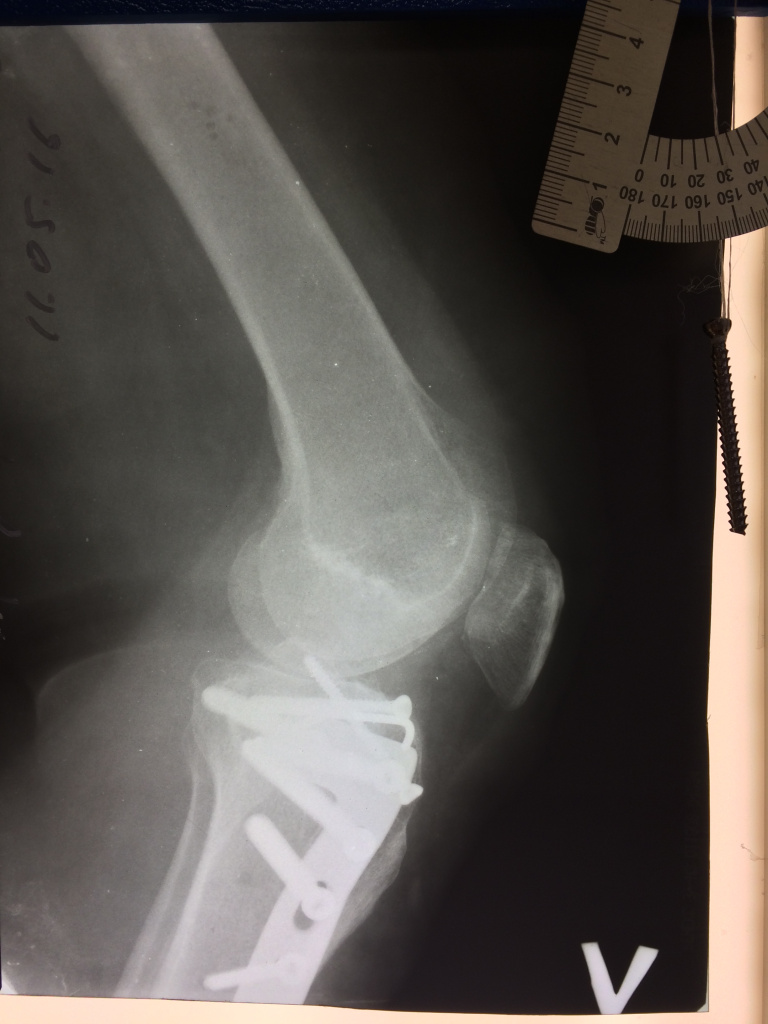

Использование материала Остеоматрикс при импрессионном оскольчатом переломе наружного мыщелка большеберцовой кости по типу Schatzker II

Использование материала Остеоматрикс при импрессионном оскольчатом переломе наружного мыщелка большеберцовой кости по типу Schatzker II.

Операция - открытая репозиция, остеосинтез большеберцовой кости опорной пластиной с костной ксенопластикой маетриалом "Остеоматрикс". На контрольных снимках в три и шесть месяцев имеется консолидация перелома, миграции фиксатора нет, имеется остеоинтеграция ксенопластического материала. Функция коленного сустава полная.